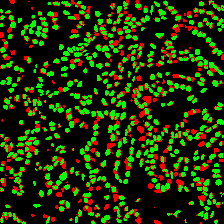

Microscopic image segmentation is a challenging task, wherein the objective is to assign semantic labels to each pixel in a given microscopic image. While convolutional neural networks (CNNs) form the foundation of many existing frameworks, they often struggle to explicitly capture long-range dependencies. Although transformers were initially devised to address this issue using self-attention, it has been proven that both local and global features are crucial for addressing diverse challenges in microscopic images, including variations in shape, size, appearance, and target region density. In this paper, we introduce SA2-Net, an attention-guided method that leverages multi-scale feature learning to effectively handle diverse structures within microscopic images. Specifically, we propose scale-aware attention (SA2) module designed to capture inherent variations in scales and shapes of microscopic regions, such as cells, for accurate segmentation. This module incorporates local attention at each level of multi-stage features, as well as global attention across multiple resolutions. Furthermore, we address the issue of blurred region boundaries (e.g., cell boundaries) by introducing a novel upsampling strategy called the Adaptive Up-Attention (AuA) module. This module enhances the discriminative ability for improved localization of microscopic regions using an explicit attention mechanism. Extensive experiments on five challenging datasets demonstrate the benefits of our SA2-Net model. Our source code is publicly available at \url{https://github.com/mustansarfiaz/SA2-Net}.